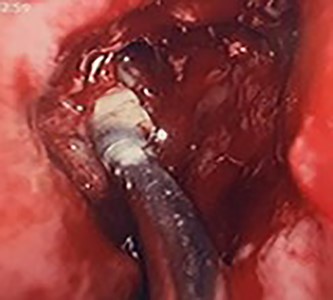

Flexible nasendoscopy offered little in terms of diagnostic benefit. An exam under anesthetic with a view to removing the ectopic tooth via endoscopic sinus surgery was warranted. Right middle turbinate trimming along with a right maxillary antrostomy was performed. The tooth was immediately identified at the antrum as depicted in Figs 4–6. The bony capsule of the tooth was entered and, on manipulation, a second ectopic tooth was identified (Fig. 7) both of which were removed en bloc. The cystic component within the maxillary sinus was marsupilized and extracted. The sinus cavity can be viewed with the utilization of 70° endoscope (Fig. 8). This facilitated bipolar cautery of the base of the cyst and confirmed the absence of an oroantral fistula.

Intra-operative image of the ectopic tooth at the right osteomeatal complex.